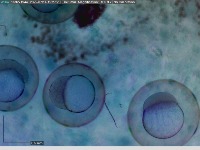

Research & Development: Researchers studying embryo development can use the AliDatabase to automate the process of identifying different stages of zeb1 cells. This can speed up research and reduce the possibility of human error in stage classification.

Medical Diagnosis: In fertility clinics or other medical settings, the AliDatabase can be utilized to identify and sort unfertilized or unhealthy zeb1 cells. This could help in diagnosing certain fertility issues and developing treatment plans.

Educational Tools: The model can be used as an educational tool for biology or medical students. By using AliDatabase, students can better understand the stages of zeb1 cell development and engage with interactive studying methods.

Pharmaceutical Testing: Companies developing drugs or treatments that impact cell growth could use AliDatabase to monitor how zeb1 cells respond at different stages to these drugs, aiding in efficacy and safety tests.

Quality Control in Lab Conditions: The model can be used to identify 'bad' or 'advanced' stages of zeb1 cells, indicating contamination or other issues in lab conditions, thereby assuring the quality of scientific experiments.